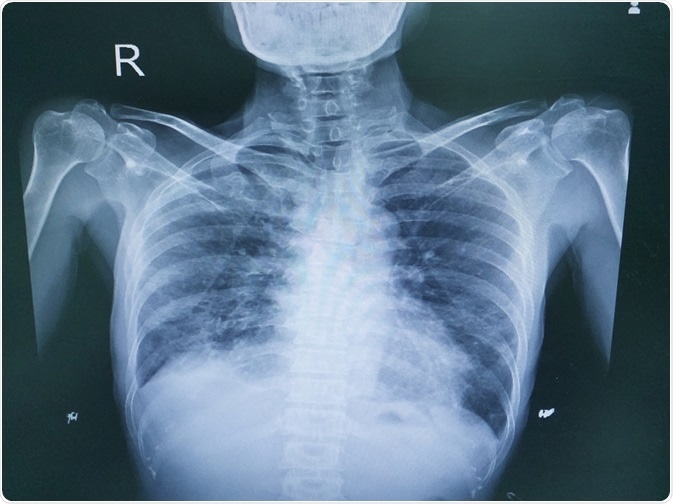

lung diseaseImage Credit: April stock / Shutterstock.com